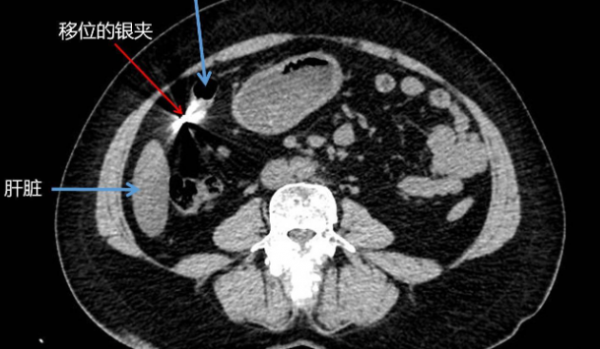

带着满心的疑惑与焦急,吴阿姨找到了我院胃肠疝和腹壁外科陈双教授求助。陈双教授再次查看CT片后,发现原本该待在右侧子宫底部输卵管的银夹子,居然一溜烟跑到了右上腹去了。怎么办呢?

尽管困难重重,但医生们并没有被难倒。陈双教授与主刀医生李英儒主治医师先让吴阿姨以站姿拍摄了X光片,再平卧复查腹部CT,撒开了一片高科技的"网",一点一点围追堵截着这个调皮乱跑的小家伙。

经过与两个月前的资料仔细比对发现,虽然体位的改变使得夹子位置不断变化,所幸移动范围暂时还是较小。不过,一个新问题又浮现出来了:采用什么方式才能又快又好地完成手术呢?

经过慎重讨论后,李英儒决定使用微创手术,在肚子上打三个小孔用腹腔镜进肚子里探查,这一探便发现,左侧正常状态的银夹还在坚守岗位--牢牢抓住输卵管,但右侧银夹却是擅自离了岗,不知去向。

腹腔镜视野在迷宫般的人体里缓缓推进,不放过一寸蛛丝马迹,终于,当李英儒轻柔地掀开结肠前方的大网膜,"逃逸"的小夹子再也藏不住了,只能乖乖地停在大网膜上,被李医生一举"抓获"!

经过谨慎细致的手术处理,李英儒帮助吴阿姨顺利地取出了移位的银夹,并根据术前患者的要求,一并取出了左侧银夹(患者已绝经),以免日后再度发生银夹"迷路"的意外。